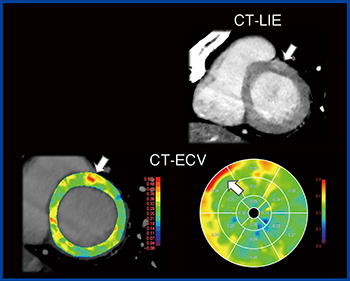

そこで,心臓CTによる心筋評価が期待されており,当院でも検討を進めている。方法は,冠動脈CTAや通常の造影CT(体幹部撮影を含む)の7〜10分後に心電図同期による遅延相撮影を追加する。これによって,CT遅延造影(Late Iodine Enhancement:LIE)やCT-ECVの算出が可能になる。Ziostation2を用いることでカラーマップ表示も可能になる(図3)。

CT-LIEは,dual energy CTを活用することで造影効果を強調してMRIのLGEに近い画像を得ることが可能になっている。また,心筋ダメージはCT-LIEだけでは評価が難しいが,CT-ECV解析を加えることで視覚的かつ定量的に判断できる。われわれは,同一症例でCTとMRIのECVの値を評価したが高い相関が認められ,CTでMRIと同等の心筋ECV評価が可能であることを報告した1)。

図3 心臓CTによる心筋評価

透析患者ではMRIのガドリニウム造影剤は禁忌となるが,CTのヨード造影剤は使用可能である。症例4は,60歳代,男性,透析患者の心筋症疑いでCTにて心筋評価を行った。前壁の接合部にCT-LIEで濃染と,CT-ECVの異常高値が認められ,心筋症と診断した(図4)。

図4 症例4:60歳代,男性,透析患者の心筋症疑いにおける心筋評価